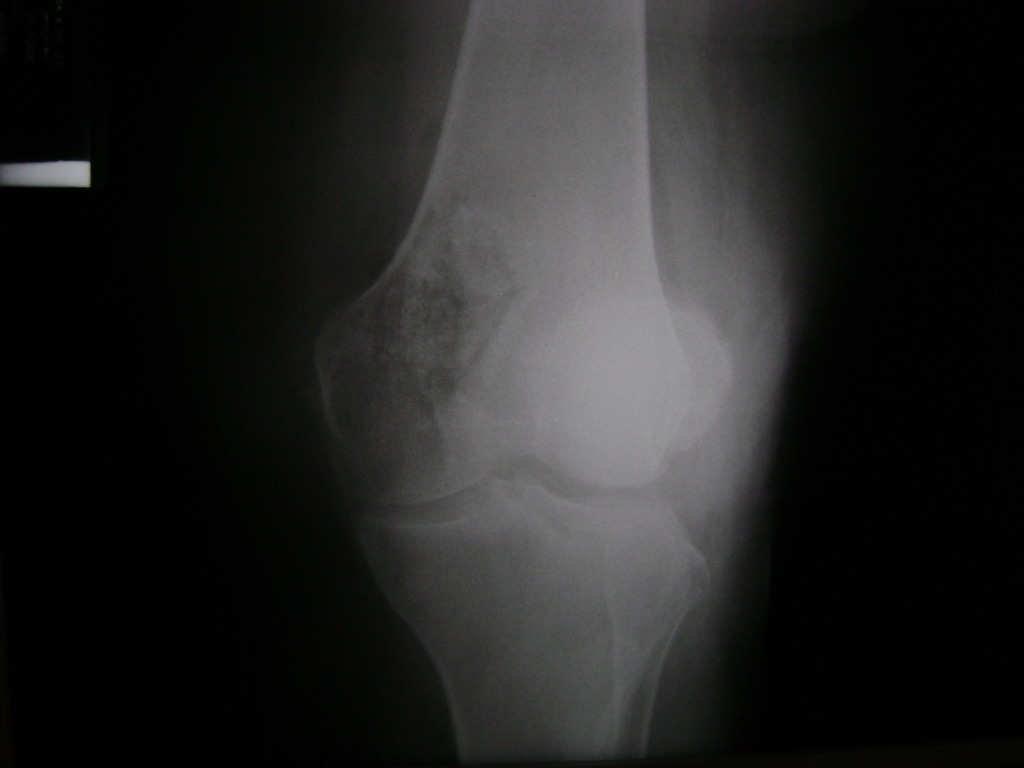

Cirugía de Fémur - Rodilla

La artroscopia de rodilla es un cirugía en el cual la estructura interna de la articulación es examinada ya sea para realizar un diagnostico o para realizar un tratamiento, este procedimiento se realiza utilizando un instrumento parecido a un pequeño tubo llamado artroscopio.